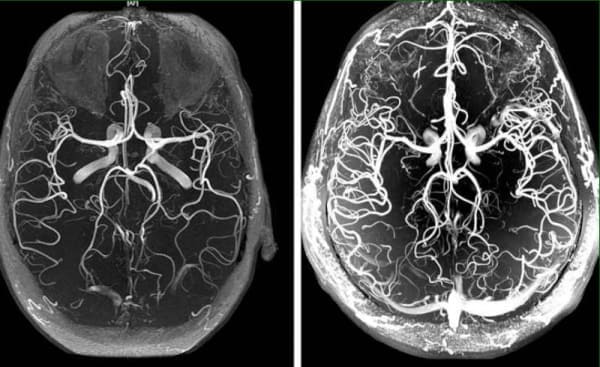

Was ist zu tun bei Kopfschmerzen, Tinnitus und tauben Gliedern? Anzeichen eines zerebralen vaskulären Angioödems.

Zerebrales vaskuläres Angioödem - das ist ein pathologischer Zustand, bei dem der normale Gefäßtonus und die Blutzirkulation in den Geweben des Gehirns gestört sind. In diesem Artikel erfahren Sie mehr über die Ursachen, Mechanismen und Symptome, wenn es Zeit ist, Alarm zu schlagen. Und auch über die schrecklichen Komplikationen dieser heimtückischen Krankheit und über den modernen Ansatz zur Behandlung, der allen zur Verfügung steht.

Das Angioödem der Hirngefäße ist das erste Anzeichen für die allgemeine "Verschmutzung" der Gefäße des Körpers mit Cholesterin: die Atherosklerose. Die Gefäße des Gehirns sind die empfindlichsten und dünnsten, daher sind sie als erste davon betroffen.

Obwohl es sich nicht um eine "akute" Krankheit handelt, ist die Verschlechterung der Hirndurchblutung sehr schleichend. Letztlich führt sie früher oder später zu einem Schlaganfall, aber vorher quält sie einen Menschen jahrelang, indem sie langsam lebenswichtige Organfunktionen abtötet und eine Vielzahl verschiedener Krankheiten verursacht.

Und je mehr Verunreinigungen sich in den Gefäßen ansammeln, desto gravierender sind die Folgen. Bei mittlerer bis mäßiger Verunreinigung der Blutgefäße des Gehirns kommt es am häufigsten zu Schlaganfällen und vollständigen oder teilweisen Lähmungen .

Die unglücklichen Gefäße leiden bereits unter den angesammelten "Schichten" von Cholesterin, die die Epithelwände angreifen und sie dünner machen. Und Vasodilatatoren dehnen die Gefäße, wodurch eine Überspannung der Wände entsteht. Wenn das Gefäß dann nicht mehr standhält und platzt, kommt es zu einem Schlaganfall.